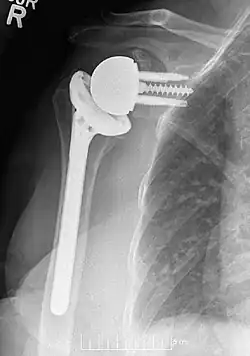

Os implantes modernos de ombro reverso consistem em várias partes. No osso da escápula, há uma placa de base metálica que se desenvolve no osso da glenoide nativa, parafusos e/ou pinos que a mantêm no lugar e um componente metálico redondo de "glenosfera" que é acoplado à placa de base por meio de vários mecanismos diferentes. No osso do úmero, normalmente há um revestimento de polietileno côncavo que se articula com a glenosfera convexa e é fixado a uma haste umeral que cresce no úmero nativo ou é cimentada no lugar. Dentro dessa estrutura básica, há diversas variações diferentes de implantes e, até o momento, não há consenso sobre qual projeto é superior, embora vários estudos tenham demonstrado alguns benefícios de determinadas combinações.[9][10][11] Um desses sistemas modernos de implante de ombro reverso é o AltiVate Reverse. Mais informações sobre esse sistema podem ser encontradas no site da DJO.